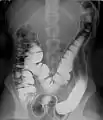

حقنة باريوم تظهر القولون بالتباين المضاعف، مستخدماً التباين الإيجابي والسلبي.